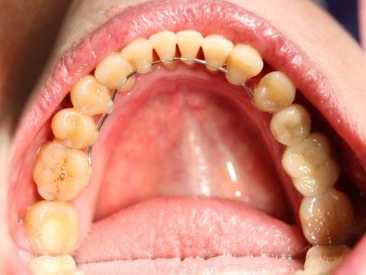

Четвертый этап заключается в установки самой шины. Бюгель, стекловолокно или винтовую конструкцию закрепляют с тыльной стороны зубного ряда и фиксируют.

- Выполнение на задней поверхности зубного ряда ровной борозды (глубина 0,5 мм).

- В сделанное углубление вставляется специальная нить.

- Проводится закрепление нити при помощи гелиокомпозита.

При выполнении шинирования нижнего ряда дополнительно проводят закрепление моляров. Для этой цели борозда высверливается на жевательной поверхности, а названная нить продевается с верхней стороны.